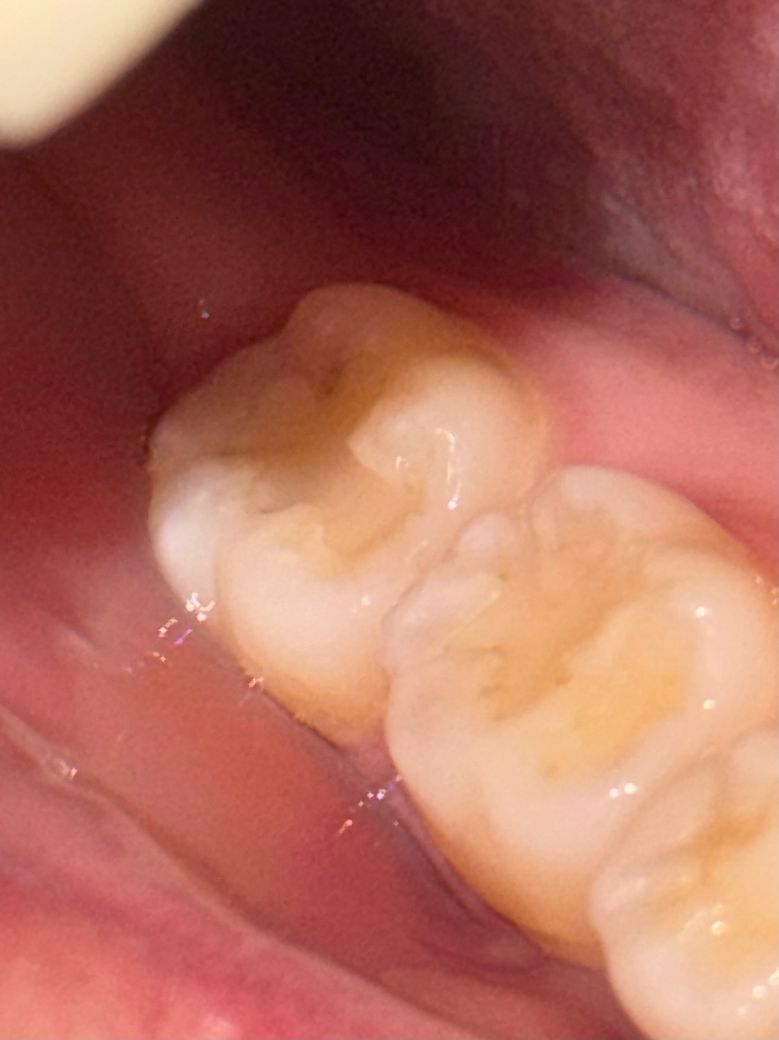

여기 충치가 생긴 게 맞는지 알고 싶습니다

최근에 치과에 갔는데 충치는 따로 없다고 해서 다행이다 하고 왔거든요 그런데 확인할 게 있어서 입 안을 보니까 맨 안쪽 어금니 레진? 채워진 부분에 회색으로 보이는 게 있어서 이게 충치가 맞을지 여쭤봅니다 사진으로는 조금 애매하게 보이는데 실제로 보면 그림자가 졌다기보다는 뭔가 있는 것처럼 보여서.... 엑스레이 찍었는데도 충치 없다고 하셨던 거라 더 잘 모르겠어서 치과 가보기 전에 여기에 먼저 올려봅니다

• 2번 째 사진

레진이 오래되다보면 치아와 레진 사이로 때가 낍니다 단순 변색이라고 보시면 될 것 같습니다

레진치료를 하고나서 시간이 지나면 틈세가 생기면서 착색이나 변색이 발생합니다. 착색이 된거니 크게 걱정은 안하셔도 됩니다.

사진으로 봤을 때 충치가 보이진 않습니다. 보철물 경계 부위가 떠 있거나 한다면 사진처럼 착색이 될 수도 있습니다. 크게 문제가 아닌 경우도 있을 수 있으니 자세한 확인을 위해서 치과에서 진료를 받아보세요